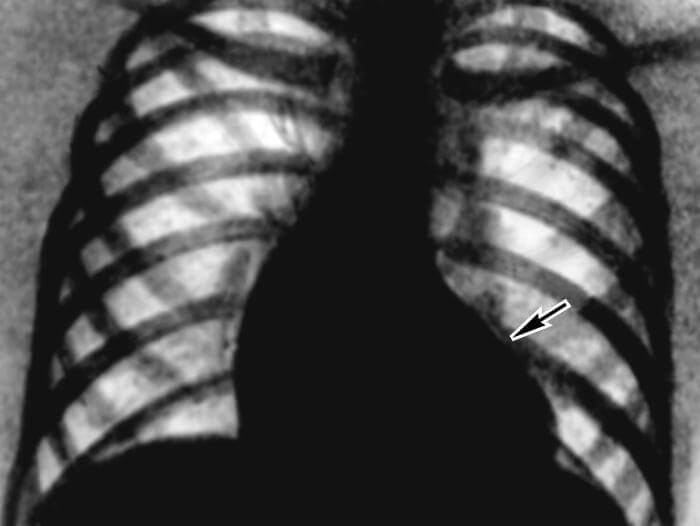

- Рентген грудной клетки — «очерчивает» границы сердца, позволяя заметить расширение полостей, характерных для стеноза, предоставляет информацию о состоянии легких, которые также страдают при сердечной недостаточности (в них часто скапливаться жидкость)